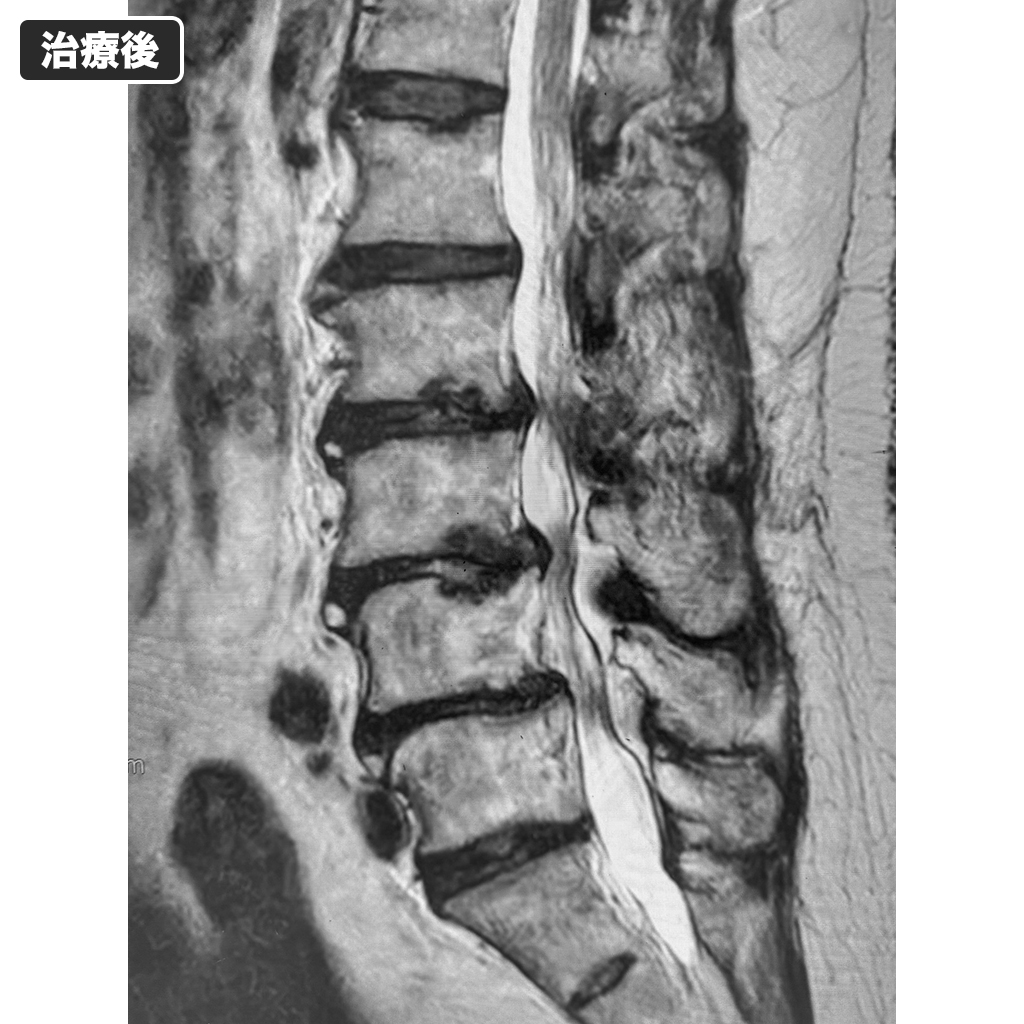

MRI検査

本日のMRI検査です。椎間板の変性など改善が見られます。ただし、治療前より皮下脂肪と内臓脂肪がかなり目立っています。

下肢の神経障害は認めませんでした。10分以上歩行すると右の臀部に突っ張ったような鈍痛を感じるとのことでした。MRI検査ではディスクシール治療部位に問題は認めませんでしたが、かなりの肥満が確認されました。以上のことから、現在出現している鈍痛は軽症であり、体重の減量を行うことで改善する可能性が高いとご説明いたしました。